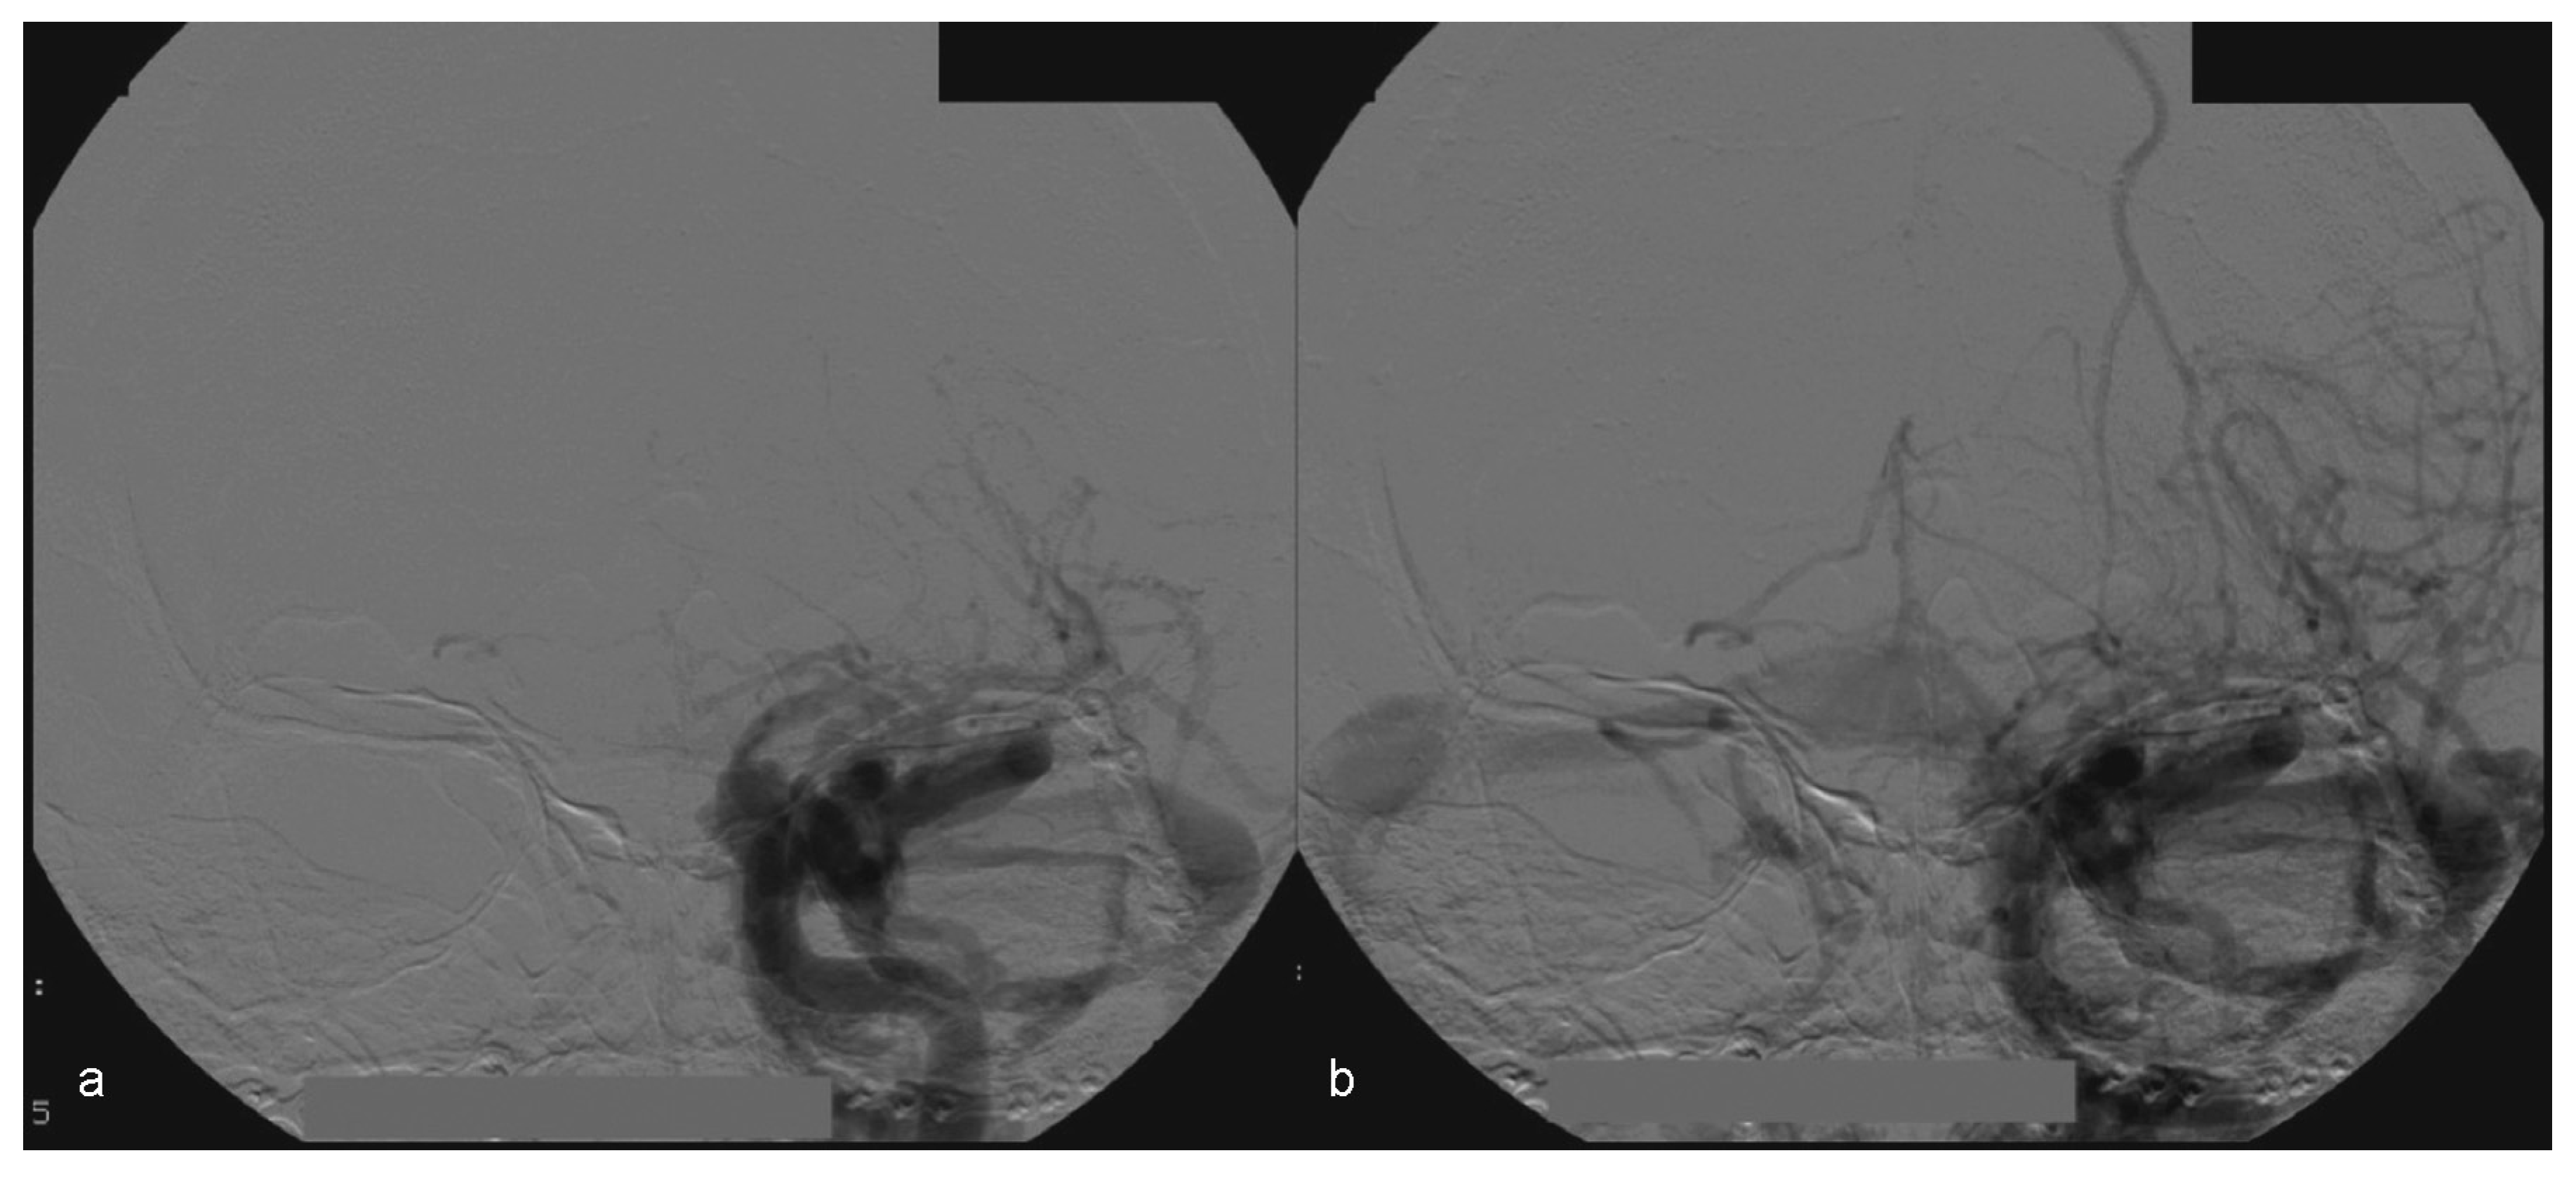

Figure 8. (a, b) Left side angiography, with coronal view, showing congestion toward the left orbit.

In this case, the right femoral artery was punctured for the bilateral carotid and vertebral angiography. Type A CCF was treated by embolization of the left traumatic cavernous aneurism using a Tracker Excel 14 microcatheter (Boston Scientific Corporation, Neurovascular Division, Freemont, CA) and a TS 14 microguide (Micro Therapeutics, Irvine, CA) to selectively catheterize the CS on the left side, by depositing nine detachable GDC microcoils (Boston Scientific Corporation) associated with a detachable balloon (Figure 9) inside it.

Figure 9. (a) Left side angiography, with coronal view, showing congestion toward the left orbit. (b) The same coronal view with occluded fistula— arrow no. 1 highlights the activated balloon and arrow no. 2 highlights the microcatheter. (c, d) Left side angiography, with sagittal view showing the detachable microcoils used for permanent carotid-cavernous fistula occlusion (arrows).